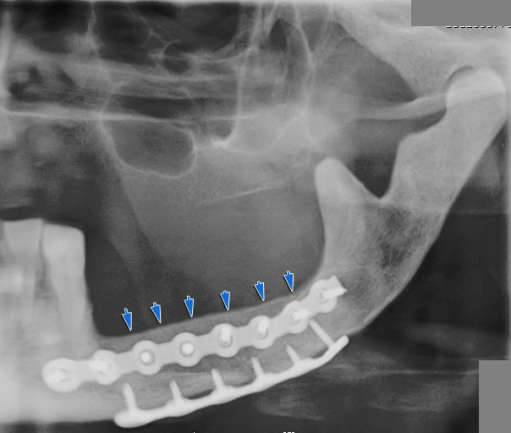

Mandibola artificiale – Ancora una volta la medicina Italiana protagonista assoluta con eccellenti risultati.Per la prima volta nel nostro paese, a Padova, è stato eseguito un trapianto artificiale di mandibola, il volto di un paziente italiano di circa 60 anni affetto da osteonecrosi è stato ricostruito con un impianto mandibolare artificiale in lega di titanio. La protesi artificiale è stata creata su misura ed ha sostituito gran parte della mandibola strutturale del volto, includendo parte del condilo e del mento, senza le quali l’essere umano non potrebbe muovere la mandibola, quindi masticare ,deglutire o parlare.

La protesi è nata da una collaborazione medico-scientifica, tra ricercatori padovani ed ingegneri di un’azienda Italiana che si occupa di sviluppare dispositivi medici. Il risultato è straordinario, una fedelissima riproduzione della mandibola.

La mandibola è stata creata in lega di Titanio, resistente e duratura. Si aprono nuove frontiere sulla personalizzazione degli impianti.

L’intervento è durato circa 5 ore, la mandibola dal peso circa 30 grammi, costruita in titanio è stata integrata perfettamente con le fasce muscolari e i nervi.

Il paziente, fanno sapere i medici, ora può masticare, parlare, respirare e deglutire normalmente e non ha più dolori. L’intervento migliora il supporto del labbro inferiore, la simmetria finale della parte inferiore del viso e la competenza delle labbra. La protesi dura una decina d’anni e all’ospedale, non al malato, costa circa 3.500 euro. «I nuovi modelli hanno dimostrato anche una buona resistenza alla chemioterapia»